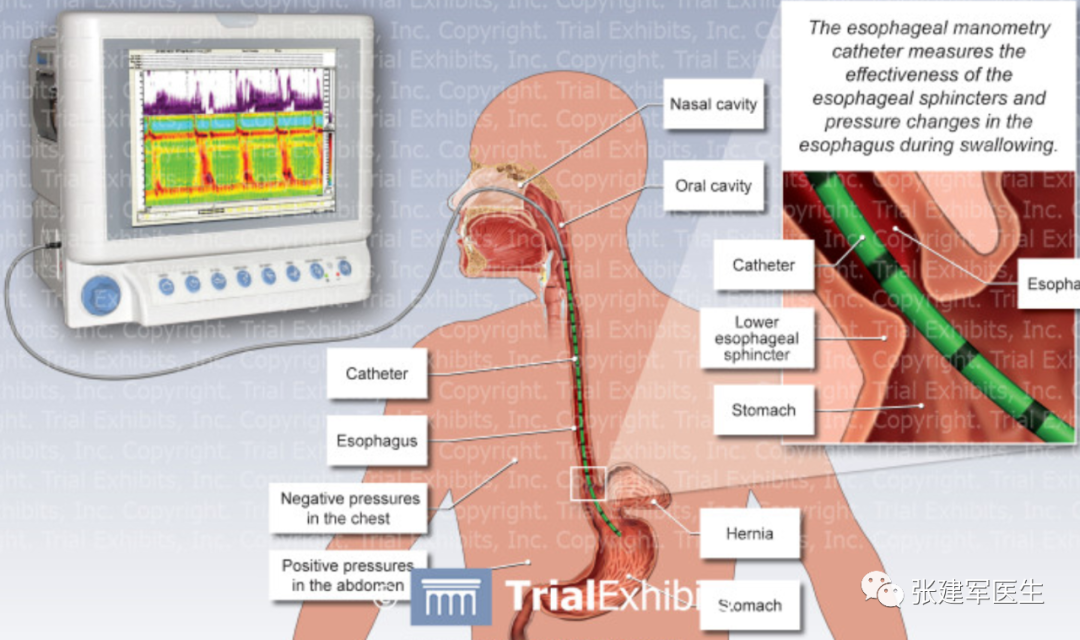

食管测压(Esophageal manometry)

使用食道内的导管来测量食管括约肌的压力,将数据转换成地形压力图。食管测压可以显示膈肌脚的水平、呼吸倒转点和膈肌脚位置,计算出食管裂孔疝滑动部分的大小,指导正确放置食道内 pH 探针。